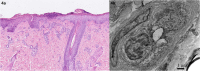

Necrotizing stomatitis is a rare, acute-onset disease that is usually associated with severely malnourished children or diminished systemic resistance. We describe a 1-year-old girl who developed necrotizing stomatitis, vasculitic rash, skin desquamation on the fingers and toes, and persistent hypertension after serologically confirmed SARS-CoV-2 infection. Her laboratory investigations revealed positive IgG anticardiolipin and IgG anti-β2 glycoprotein antibodies, and biopsy of the mucosa of the lower jaw showed necrosis and endothelial damage with mural thrombi. Swollen endothelial cells of small veins in the upper dermis were confirmed also by electron microscopy. As illustrated by our case, necrotizing stomatitis may develop as a rare complication associated with SARS-CoV-2 infection and can be considered as a part of the clinical spectrum of COVID-19 vasculopathy. The pathogenic mechanism could involve a consequence of inflammatory events with vasculopathy, hypercoagulability, and damage of endothelial cells as a response to SARS-CoV-2 infection.